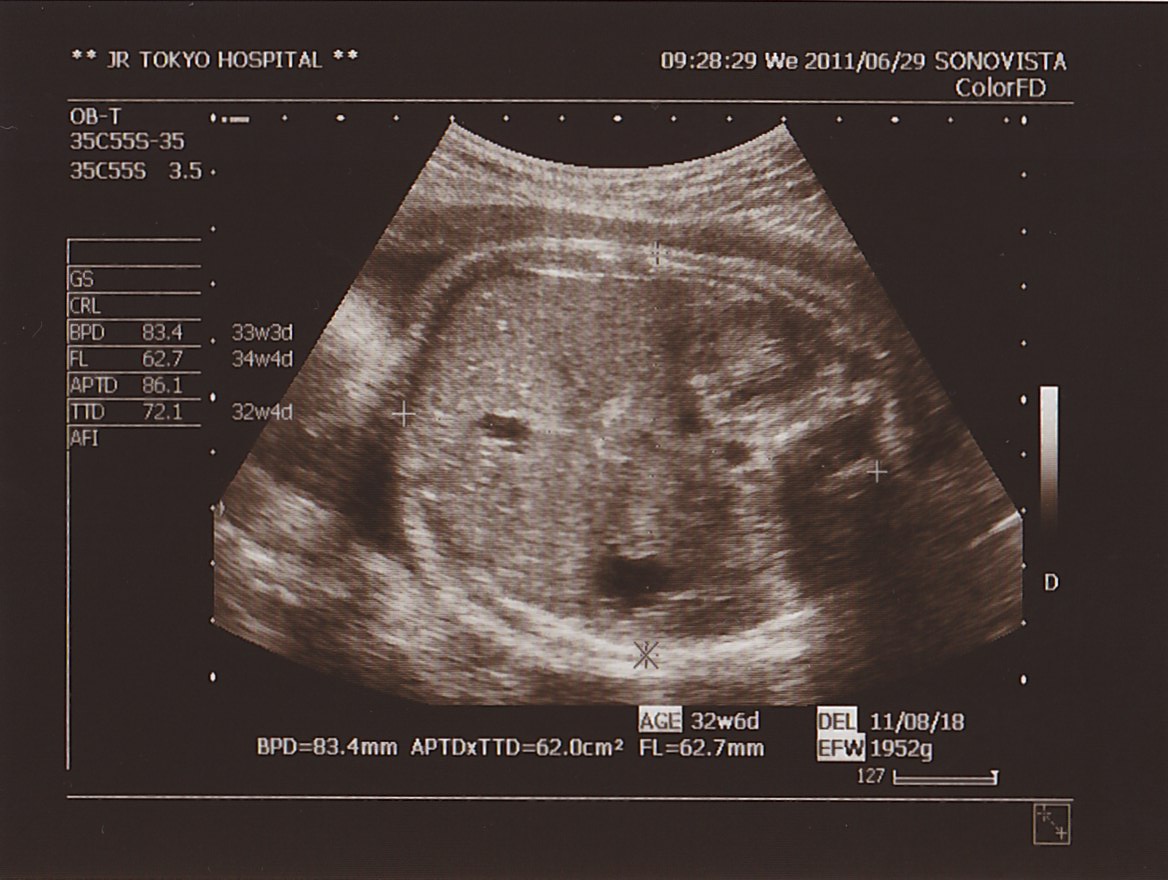

▲ 相変わらず 代わり映えのない エコー写真。

それでは  本日の 測定値。

BPD ( 頭の直径 ) : 83.4ミリ

APTD × TTD ( お腹まわり ) : 62.0平方センチメートル

FL ( 太もも骨長 ) : 62.7ミリ

EFW ( 推定体重 ) : 1952グラム

想定週数 : 32w 6d

でした。

今回も サイズ 動き ともに 順調。